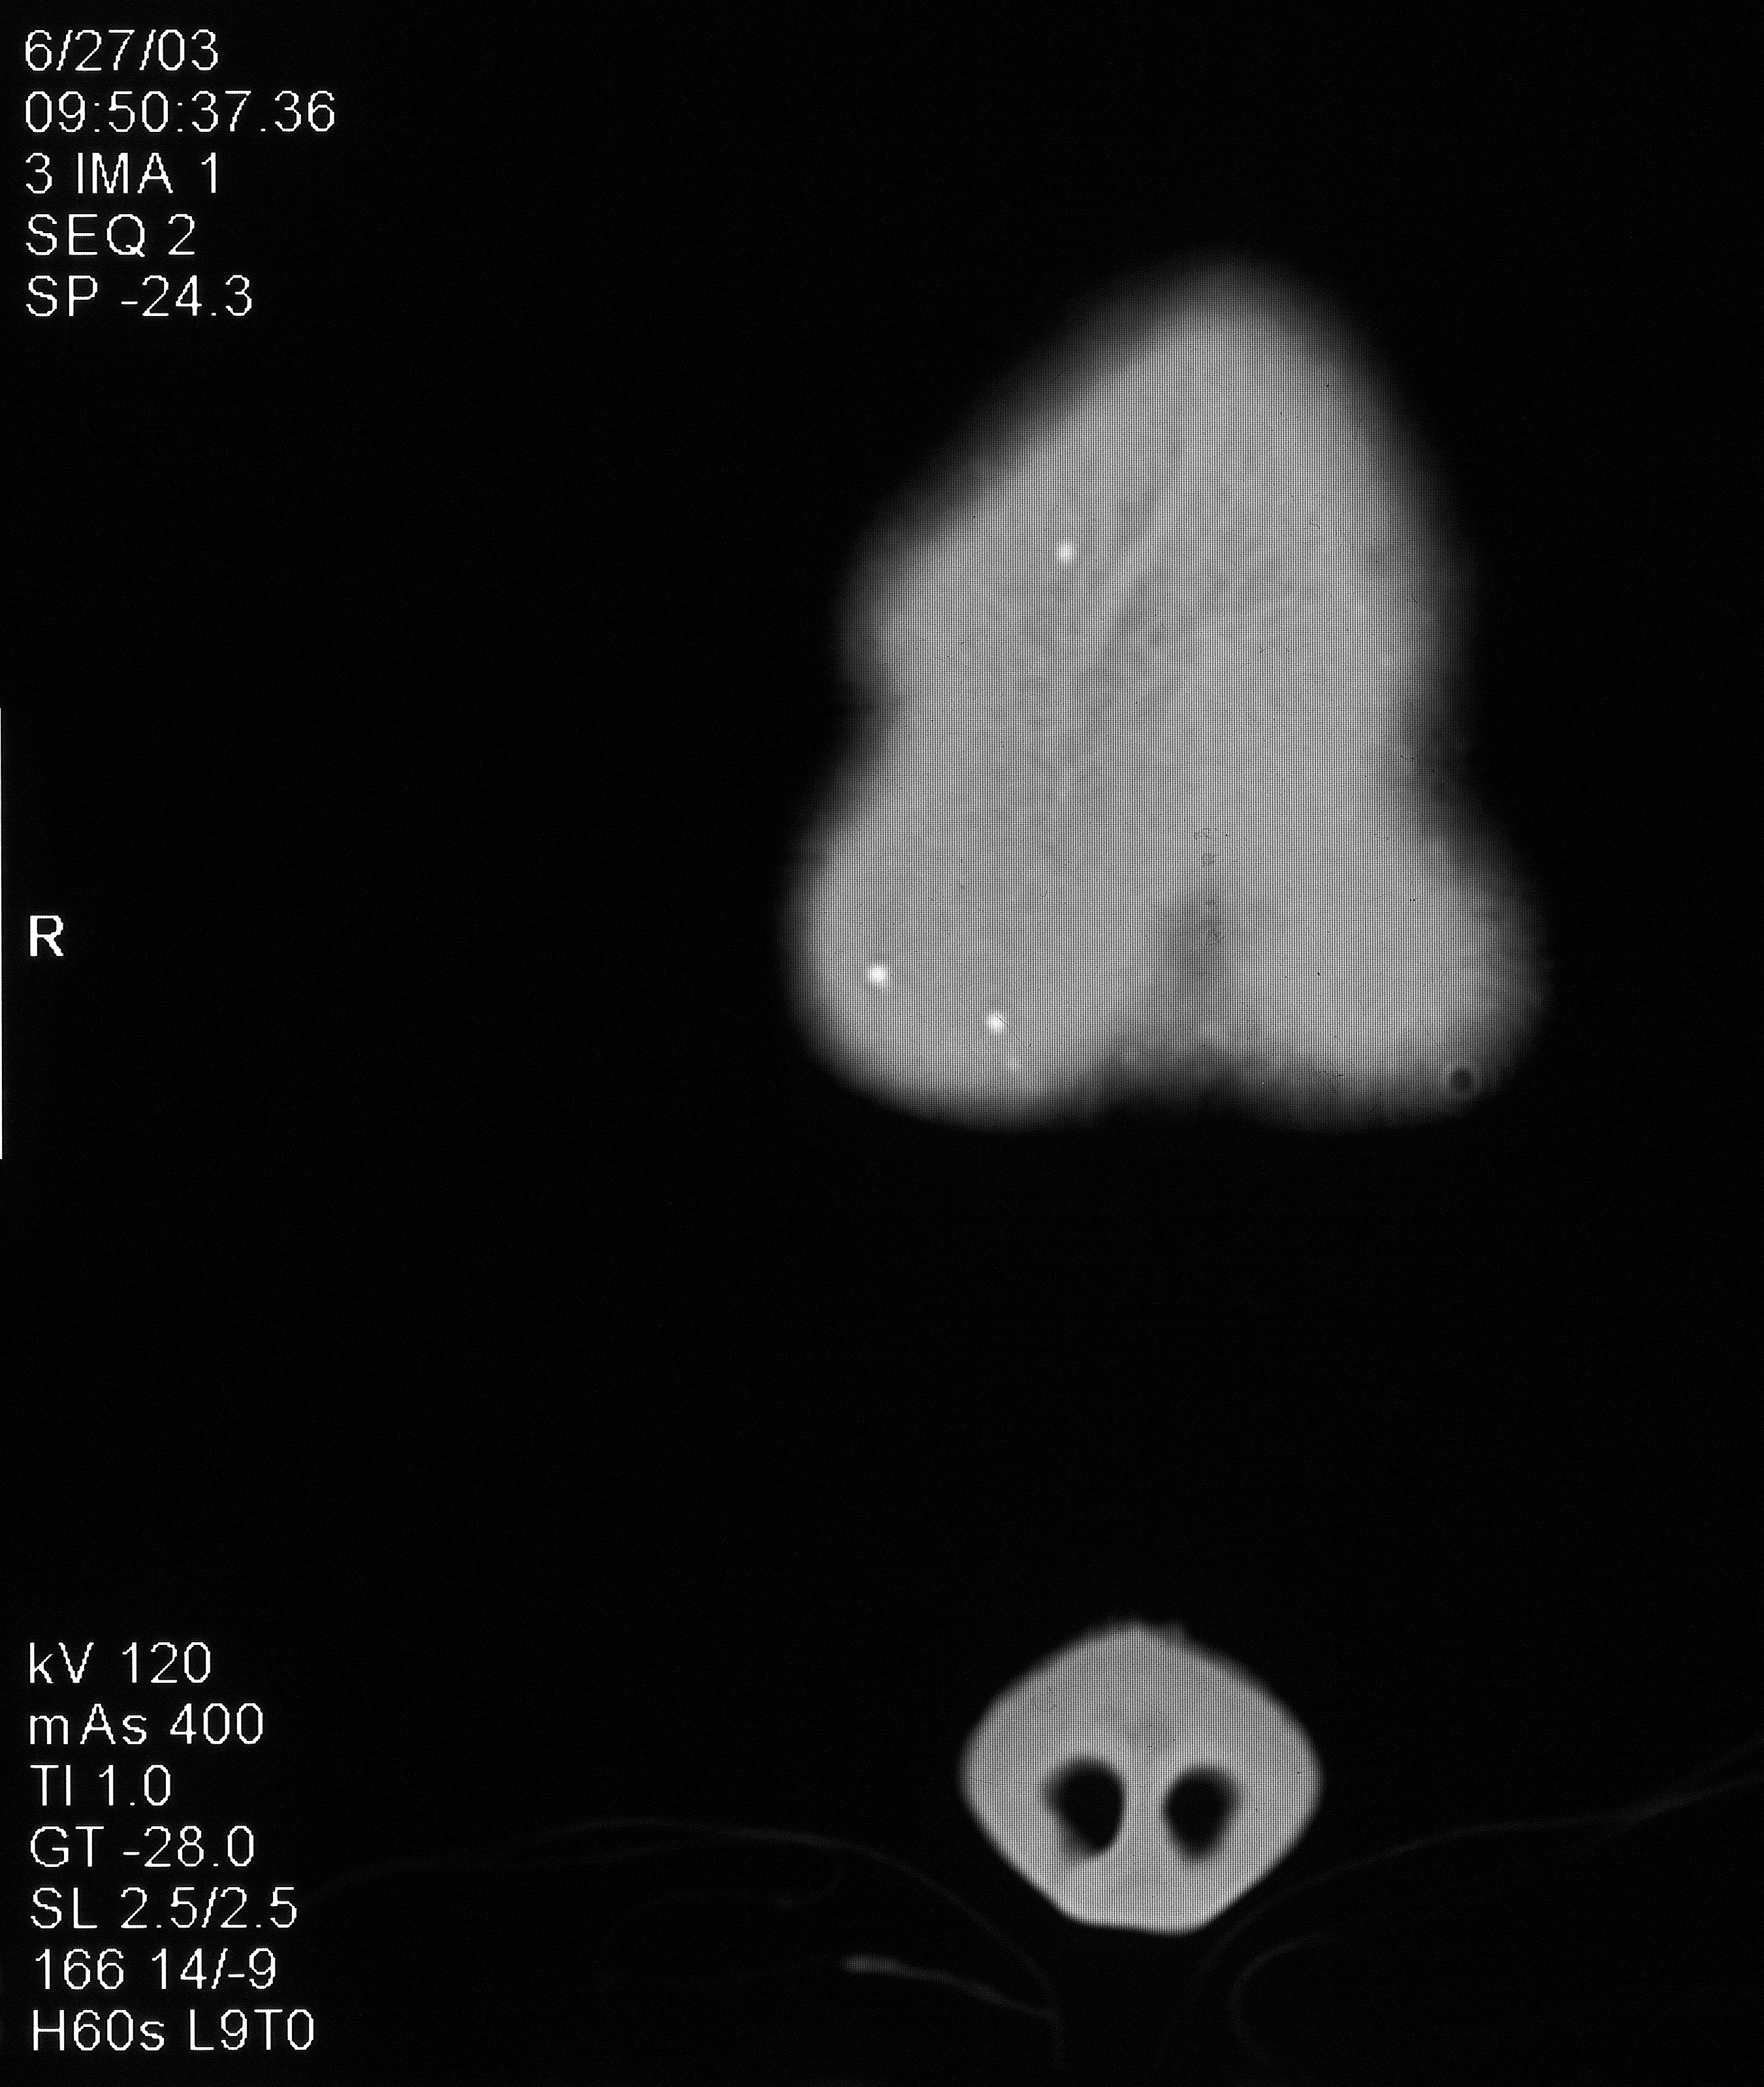

“This is a CT scan of me from June 27, 2003, that shows implanted microchips in my forehead. This is a 1/8″ slice closest to the surface. Notice the circular one on the right side of the scan.”

“This one is from a slice 1/4” deeper, showing the front of my skull. When zoomed in, you can see concentric circles emanating from the circular chip from the transmissions disrupting the CT scan. This chip is transmitting my location and/or my thoughts to the agency monitoring me.